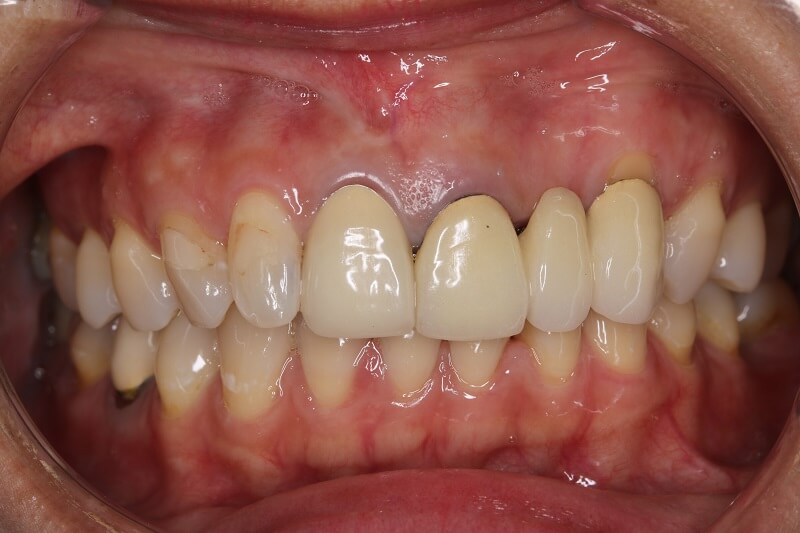

缺牙多顆

案例一

術前

術後